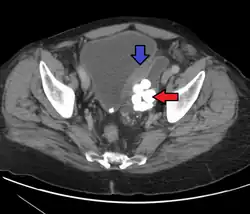

| Histopathology of transitional carcinoma of the urinary bladder. Transurethral biopsy. Hematoxylin and eosin stain. | |

Transitional cell carcinoma is a type of cancer that arises from the transitional epithelium, a tissue lining the inner surface of these hollow organs.[1] It typically occurs in the urothelium of the urinary system; in that case, it is also called urothelial carcinoma. It is the most common type of bladder cancer and cancer of the ureter, urethra, and urachus. Symptoms of urothelial carcinoma in the bladder include hematuria (blood in the urine). Diagnosis includes urine analysis and imaging of the urinary tract (cystoscopy).